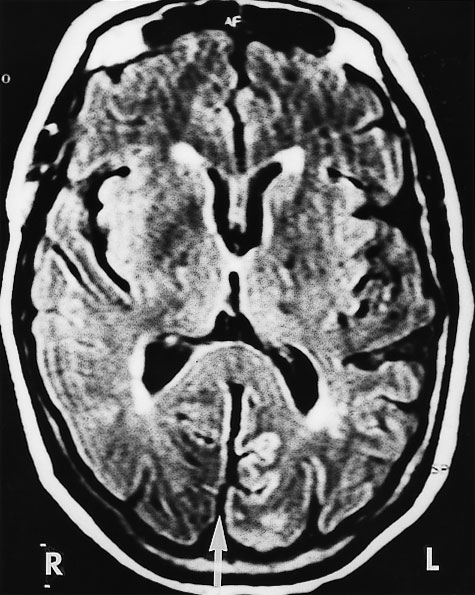

Computed tomography (CT) brain scan was performed three hours after the completion of coronary angiography. No additional contrast was used. The CT brain scan (Box 1) showed marked bilateral contrast enhancement of the occipital lobes and no evidence of a cerebral haemorrhage. Intravenous heparin treatment was commenced. By the following day, she was able to see shapes and shadows but had persistent headache and nausea. A repeat CT brain scan did not show any residual abnormality. During the next 48 hours, her vision progressively returned. She described flashing lights in her right eye and had evidence of right homonymous hemianopia. Magnetic resonance imaging (MRI) showed increased signals in the grey matter of the medial aspect of the left occipital lobe, on a background of longstanding mild ischaemic changes consistent with her age and cardiac risk factors (Box 2A). Magnetic resonance angiography (MRA) showed patency of both posterior cerebral arteries, with dilatation of branches supplying the left occipital lobe (Box 2B). Heparin therapy was ceased, as there was no evidence of acute thromboembolism or acute infarction. She fully regained her vision five days after coronary angiography.

These mechanisms seem possible in our patient, and they were supported by the results of imaging studies. There were bilateral occipital lobe changes when she had clinical cortical blindness (Box 1), representing oedema and passage of contrast across the blood–brain barrier. Cortical blindness is synonymous with bilateral homonymous hemianopia from involvement of the occipital cortex.1 When our patient was recovering and exhibiting right homonymous hemianopia, there were MRI changes in the left occipital gyrus, and differences in the calibre of the vessels on the two sides (Box 2).

2: Magnetic resonance imaging (MRI) of the patient's head 48 hours after coronary angiography, when she had right homonymous hemianopia

A: MRI (FLAIR image) shows increased signals in the medial aspect of the left (compared with the right) occipital gyrus separated by a fissure (arrow). Scattered foci of longstanding ischaemic damage on the rim of the lateral ventricles and frontal horns are consistent with the patient's age and risk factors.

A: MRI (FLAIR image) shows increased signals in the medial aspect of the left (compared with the right) occipital gyrus separated by a fissure (arrow). Scattered foci of longstanding ischaemic damage on the rim of the lateral ventricles and frontal horns are consistent with the patient's age and risk factors.